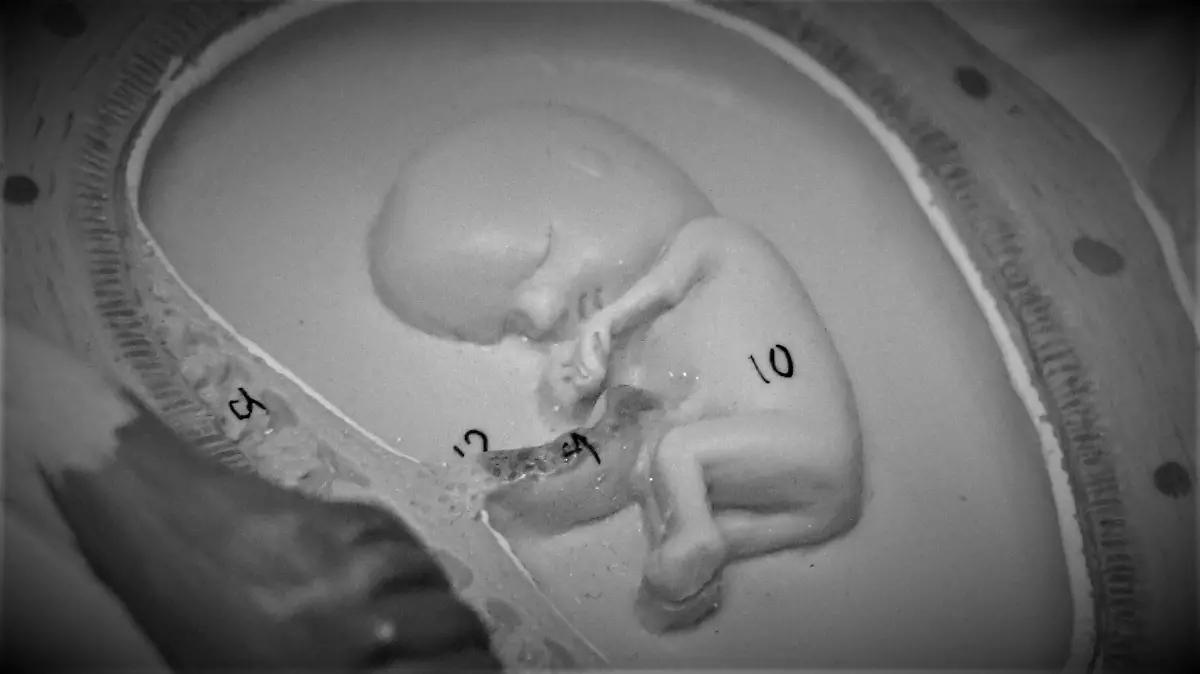

“¿Y si el silencio después del parto pesara más que la pérdida?” Te contamos por qué miles de mujeres lo viven así

Buscan garantizar derechos y protocolos humanos para mujeres que pierden a sus bebés antes o durante el parto